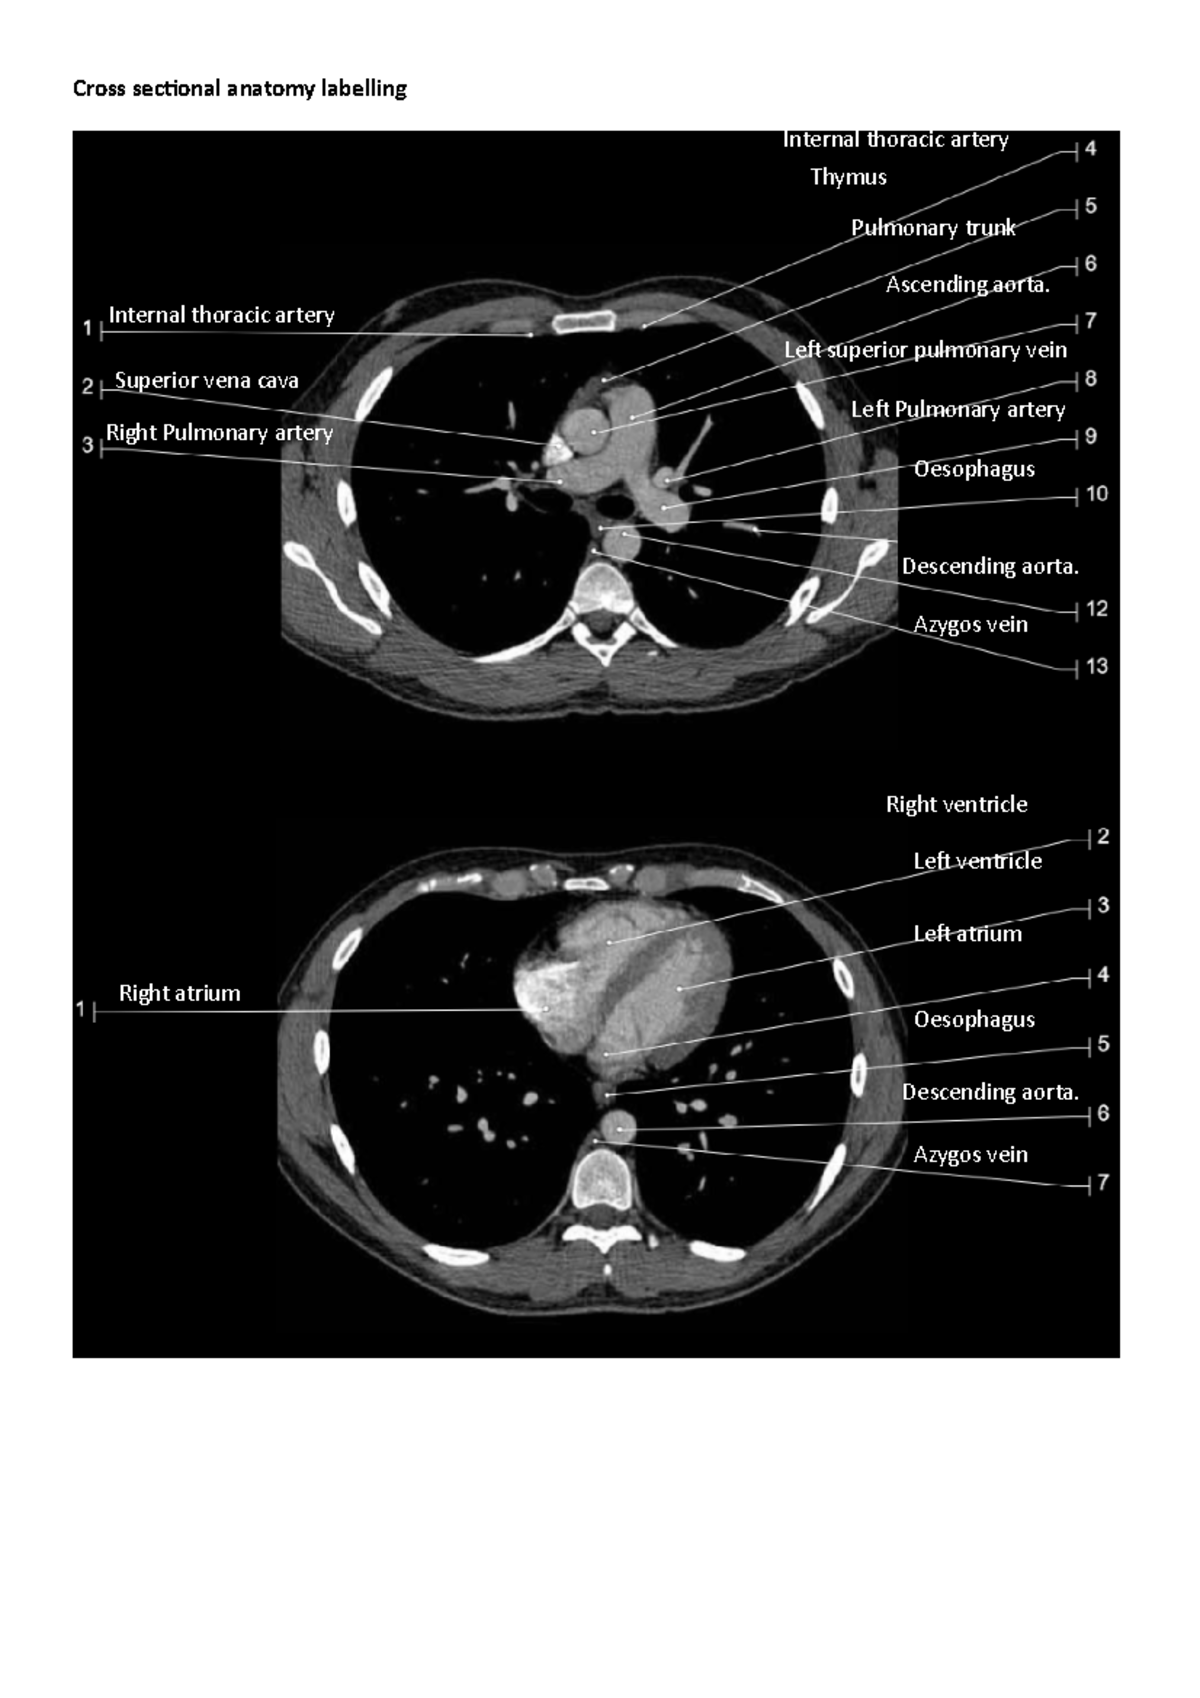

Cross sectional anatomy labelling practice Cross sectional anatomy Cross Sectional Imaging Examples the main focus of this book is to summarize the most common disease process of the liver briefly, to define the mr imaging features with. Three relatively recent imaging techniques, computed tomography. Cross Sectional Imaging Examples.